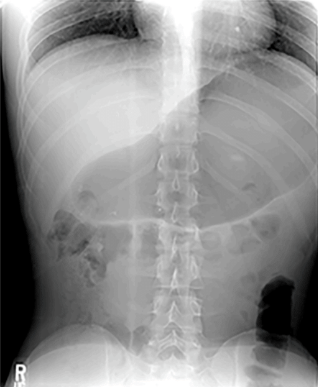

Fig. 1–Abdominal XR of a patient with R-CPD and gaseous abdominal bloating